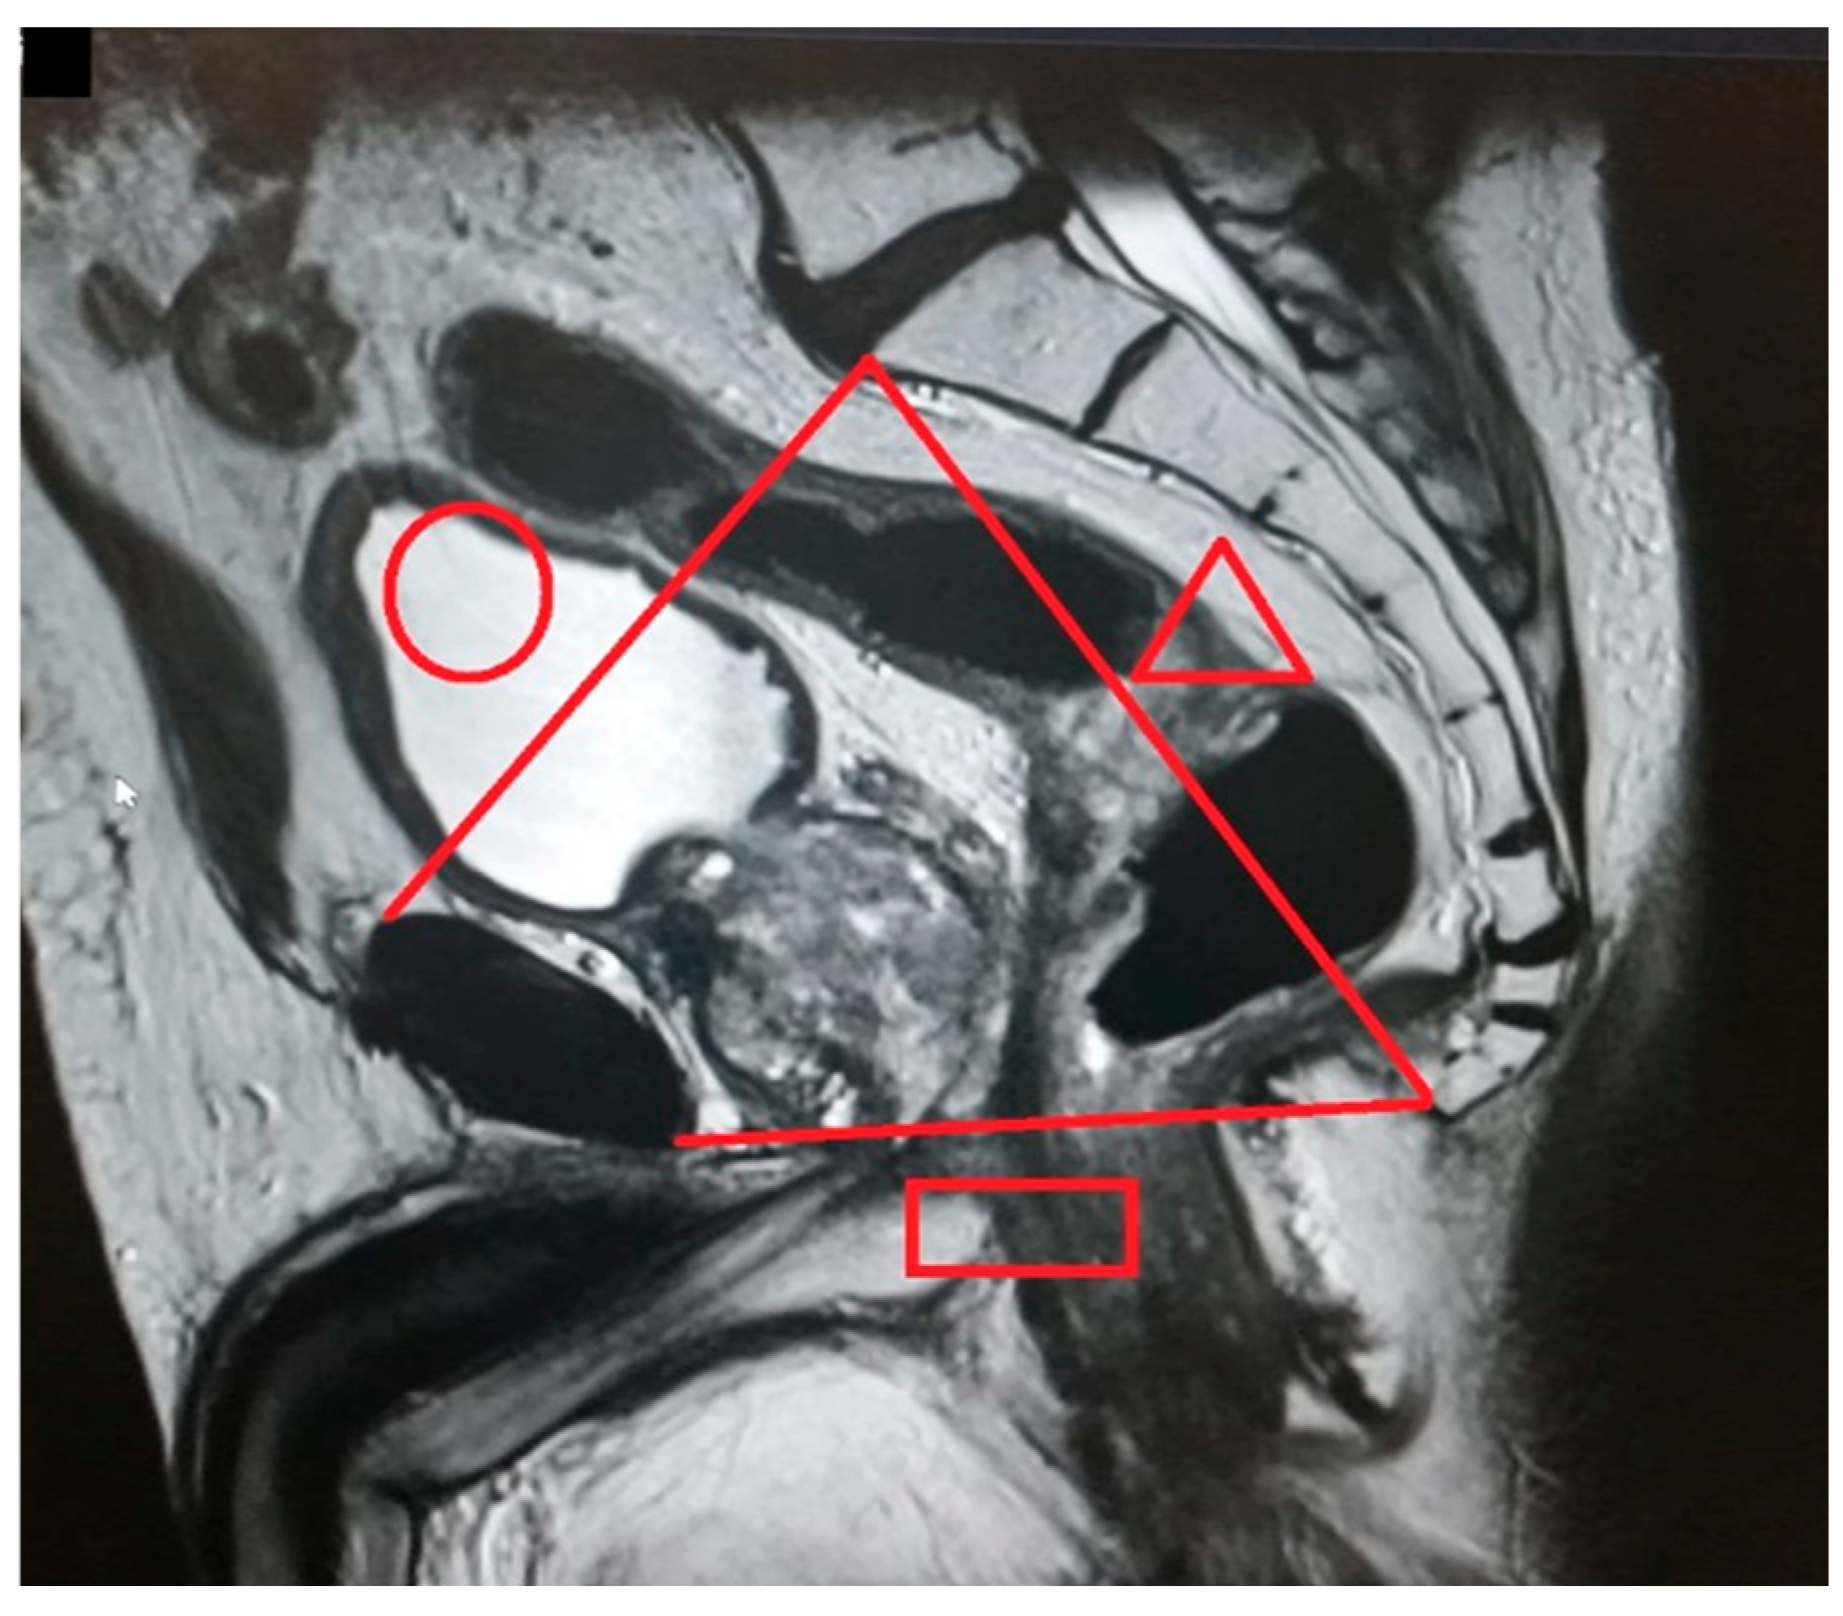

Figure 2.

Pelvic inlet (circle): distance from the superior aspect of the pubic symphysis to the promontory). Pelvic outlet (rectangle): distance from the inferior aspect of the pubic symphysis to the tip of the coccyx). Pelvic depth (triangle): distance from the promontory to the tip of the coccyx.